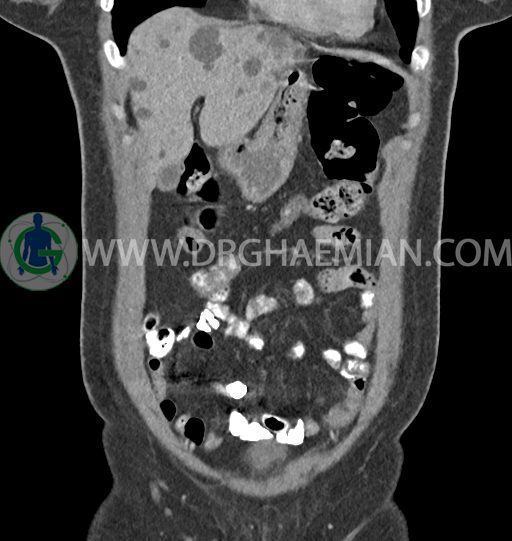

سی تی اسکن شکم و لگن با استفاده از اشعات ایکس تصاویر عرضی از ناحیه شکم و لگن ایجاد میکند. در این کیس کبد پلی کیستیک، کیست در تخمدان چپ، توده در دیواره سرویکس و اسپوندیلولایزیس دو طرفه مهره L5 دیده می شود.

در سی تی اسکن اسپیرال شکم و لگن – 5Phasic (بدون کنتراست – با کنتراست در فاز آرتریال ، پورتال و تاخیری 5 دقیقه و 10 دقیقه، مولتی دیدکتور 16 با مقاطع ظریف و بازسازی های ساژیتال و کرونال) :

-ضایعات سیستیک فراوان به قطر 5 تا 30mm پراکنده در کبد بدون جزء سالید، بدون septation و بدون اینهنسمنت پس از تزریق کنتراست مطرح کننده polycystic liver disease

-کیست ساده به قطر 31mm در تخمدان چپ

-توده هیپودنس به قطر 13mm در دیواره قدامی سرویکس نیازمند مطابقت سونولوژیک

-اسپوندیلولایزیس دو طرفه L5 همراه با آنترولیستزیس gread 1 و تغییرات DJD در L5/S1

مشهود است.